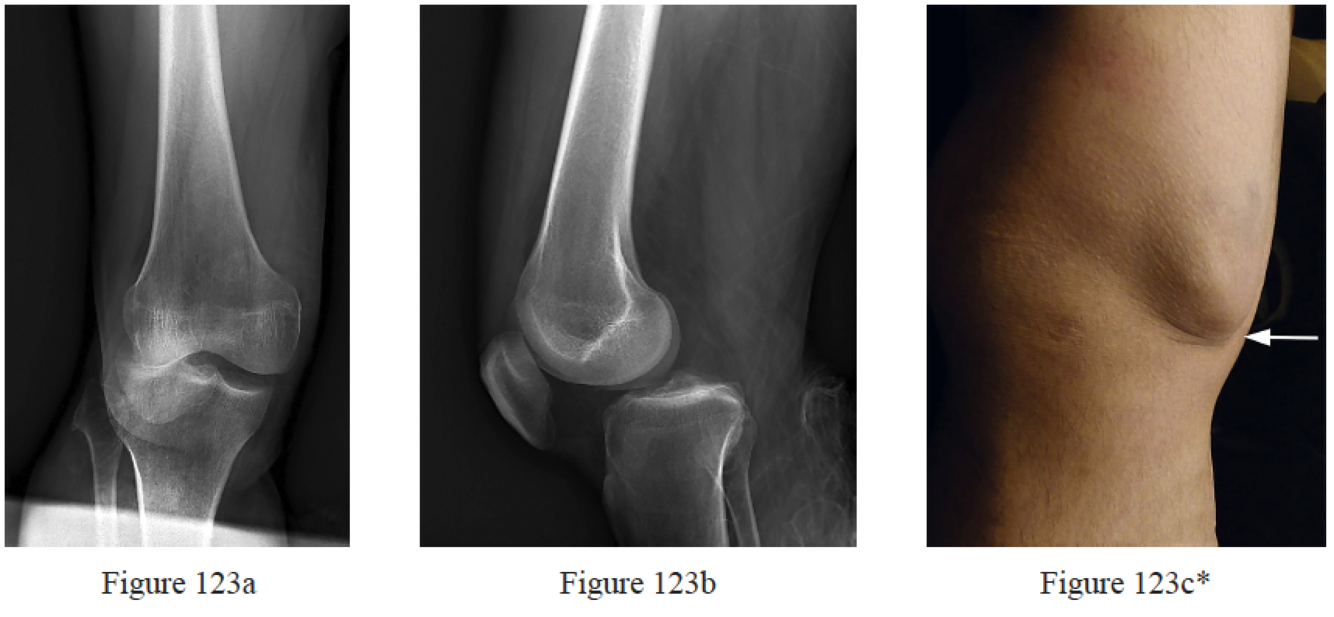

Rihn JA, Groff YJ, Harner CD, Cha PS. The acutely dislocated knee: evaluation and management. J Am Acad Orthop Surg. 2004 Sep-Oct;12(5):334-46. Review. PubMed PMID: 15469228.

Wand JS. A physical sign denoting irreducibility of a dislocated knee. J Bone Joint Surg Br. 1989 Nov;71(5):862. PubMed PMID: 2584265.